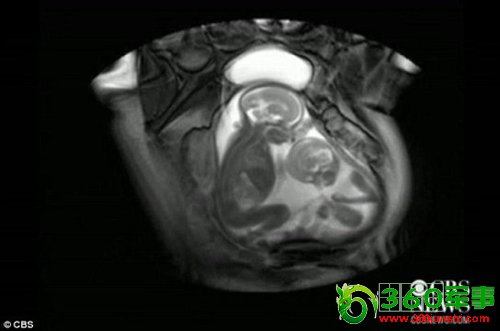

核磁共振成像技术显示,一对双胞胎在妈妈肚子里拳脚相向“掐架”